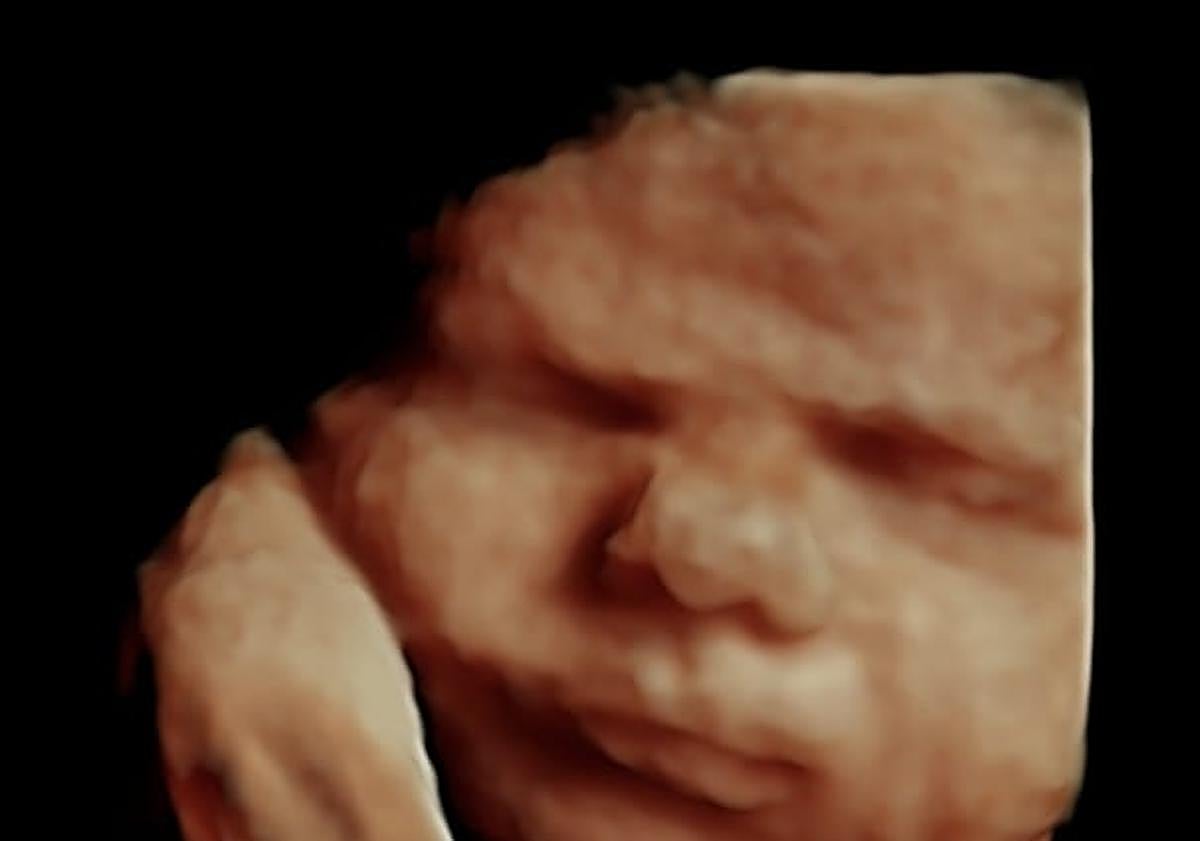

Según detalla Eduardo, la base de todas las ecografías es el 2D: «Estas ecografías nos permiten observar al bebé de forma segura y no invasiva para analizar su crecimiento». Y desde ahí llega todo lo demás. Por ejemplo, la ecografía 3D muestra al bebé en tres dimensiones en una imagen estática. Y el 4D es lo mismo que el 3D pero en vídeo, lo que permite «registrar gestos y expresiones».

«El 5D es un paso más allá del 4D, mejora la iluminación y el sombreado. Por eso ya no utilizamos el 4D y pasamos del 3D directamente al 5D», detalla el propietario de NeoVida 5D. Todo esto les permite ofrecer servicios como «ecografías emocionales» que permiten a madres y padres a generar un vínculo de forma temprana con el bebé. Sin olvidar las ecografías en 8K, que utilizan la IA para, mediante una ecografía en 3D, hacer una fotografía hiperrrealista del bebé.